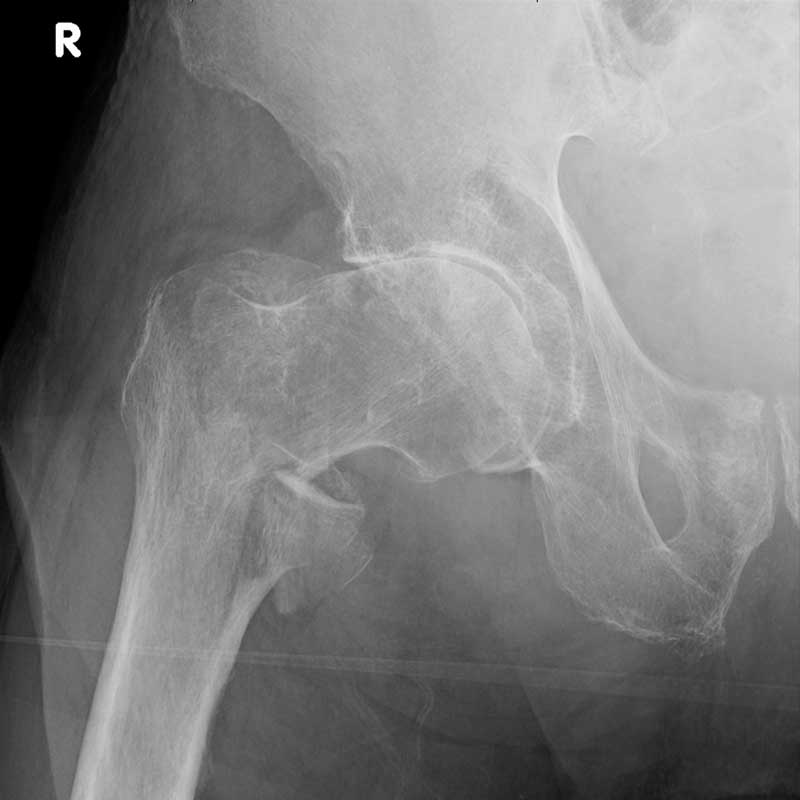

. Röntgenaufnahme eines rechten Hüftgelenks, zeigt Knochen und Gelenkstruktur.

AP-Hüfte rechts mit pertrochantärer Femurfraktur

Die Notfall- und Traumaradiologie ist ein wesentlicher Bestandteil der diagnostischen Radiologie. Hier erkennen wir in enger Zusammenarbeit mit den Ärztinnen und Ärzten der Notaufnahme die Verletzungen von verunfallten und schwerverletzten Patientinnen und Patienten. Darüber hinaus spielt sie auch bei leichteren, alltäglichen Verletzungen eine wichtige Rolle. Wir setzen modernste bildgebende Verfahren ein, um die Verletzungen genau zu untersuchen.

In Notfallsituationen ermöglichen wir innerhalb weniger Minuten ein optimiertes Therapieverfahren, indem wir das Verletzungsmuster in der Multislice-Computertomografie beurteilen. Komplexe Verletzungsmuster erfassen wir so in kürzester Zeit, klassifizieren und kommunizieren sie leitliniengerecht.

Neben der Behandlung von schwerverletzten Patientinnen und Patienten befasst sich die Notfall- und Traumaradiologie auch mit dem breiten Spektrum leichterer, nicht lebensbedrohlicher Verletzungen. Diese treten vor allem im Alltag auf. Es handelt sich u.a. um Prellungen, Platzwunden oder Knochenbrüche. Um deren Ausmaß zu beurteilen, haben wir neben der Computertomografie (CT) auch die Magnetresonanztomografie (MRT) sowie die Röntgen- und Ultraschalldiagnostik.